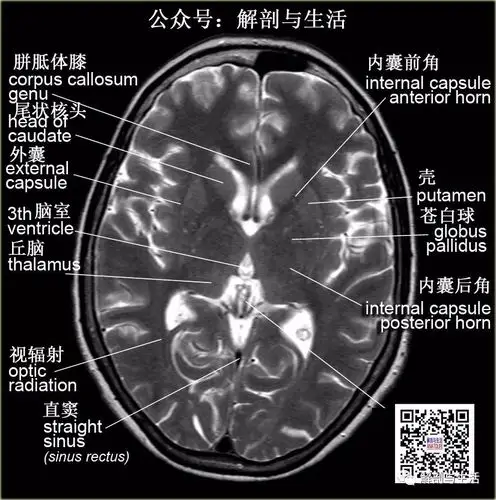

基底核基底神经节